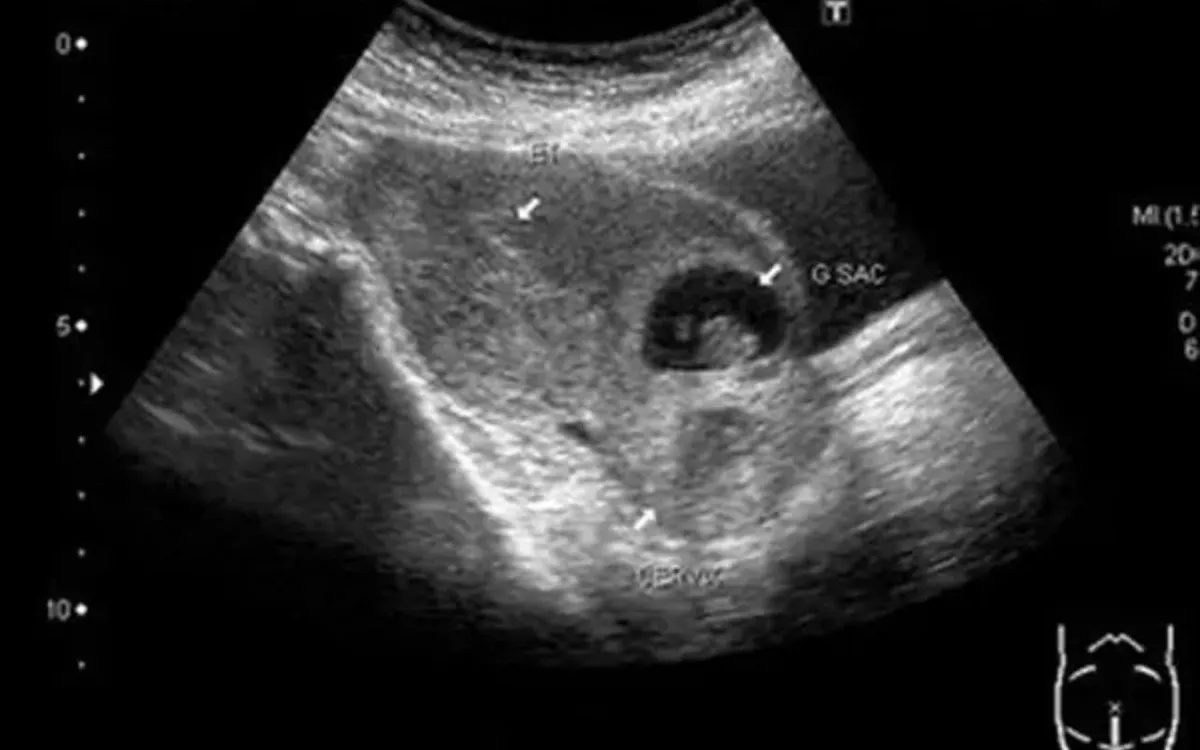

Chỉ vài giờ sau dùng thuốc, bệnh nhân xuất hiện chảy máu âm đạo ồ ạt, lượng máu nhiều, nhanh chóng rơi vào tình trạng nguy hiểm và được đưa đến bệnh viện cấp cứu. Qua thăm khám và siêu âm, các bác sĩ xác định đây là trường hợp chửa tại vết mổ lấy thai cũ - một dạng đặc biệt nguy hiểm của thai ngoài tử cung, khi túi thai làm tổ ngay tại vị trí sẹo mổ đẻ.